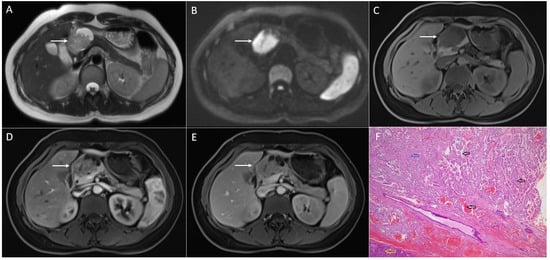

2. Typical Imaging Presentation of Solid Pseudopapillary Neoplasms